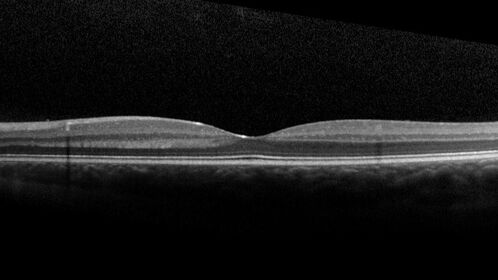

Coats' Disease - 8-year-old boy - Asymptomatic

Normal vision - Lesion picked up on examination